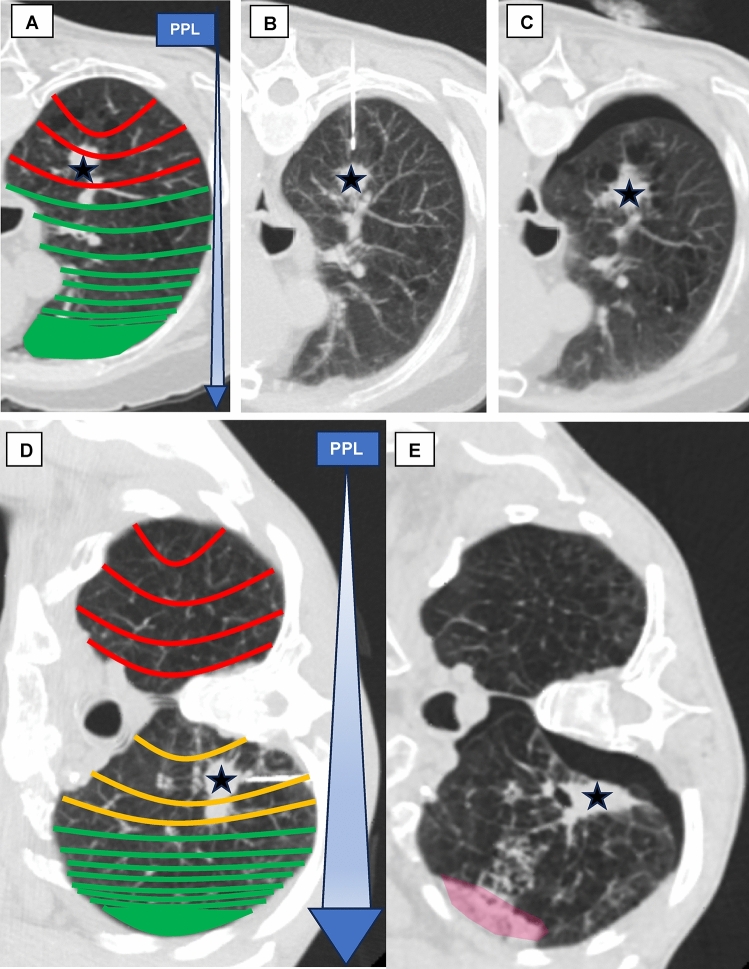

Purpose: The study aimed to evaluate whether the relative height (RH) of the entry point (EP) during CT-guided lung biopsies, adjusted for patient positioning, can predict the risk of pneumothorax during the intervention, leveraging the gravitational effects on pleural pressure.

Materials and methods: We retrospectively analyzed 128 percutaneous CT-guided lung biopsies performed at a single center between January 2018 and December 2023. Patients were grouped based on pneumothorax occurrence. Various measurement methods indirectly assessed the influence of gravitational force on pleural pressure, focusing on the RH at the EP with prone positioning adjustments (PP). Other confounding factors like patient demographics, lesion characteristics, pre-puncture fluid administration and other procedural details were assessed. Test performance metrics were compared using Chi-Square, Fisher's exact, and Mann-Whitney U tests. Univariate and binomial logistic regression assessed the influence of different parameters on pneumothorax occurrence.

Results: All measurements of lower RH at EP and pre-puncture fluid administration were significantly associated with a reduced incidence of peri-interventional pneumothorax (p < 0.01). The RH at EP adjusted for the prone position demonstrated the best predictive performance (AUC = 0.844). After adjusting for various confounding factors, both lower RH at EP adjusted for the prone position (OR 110.114, p < 0.001) and pleural fluid administration (OR 0.011, p = 0.011) remained independently associated with a lower risk of pneumothorax.

Conclusion: Strategic use of gravity by selecting the lowest possible entry point, ideally positioning the patient laterally, combined with pre-puncture pleural fluid administration, could be the key to reducing pneumothorax in CT-guided lung biopsies.